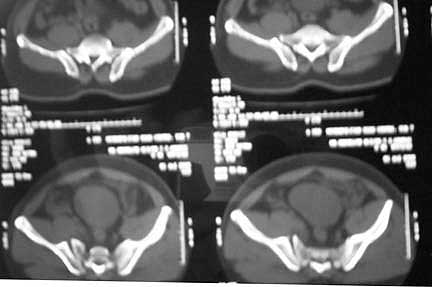

Middle aged male who was injured when a log of wood fell on him ina saw mill. Haemodynamically patient stable. No visceral injuries detected. The following musculoskeletal injuries detected: 1) Closed fracture femur. 2) Pubic symphysis disruption. 3) Right inf pubic rami fracture. 4) Right acetabular fracture. Head of femur located. 5) Right Sacroiliac joint anterior opening.

Your plan sounds fine. The acetabular fracture looks like a high ramus fracture that happens to enter the acetabulum. The CT scan is blurry, and you haven't provided any oblique views of the acetabulum - but my guess is that the 'tab is concentric.

Here are the post op pictures.